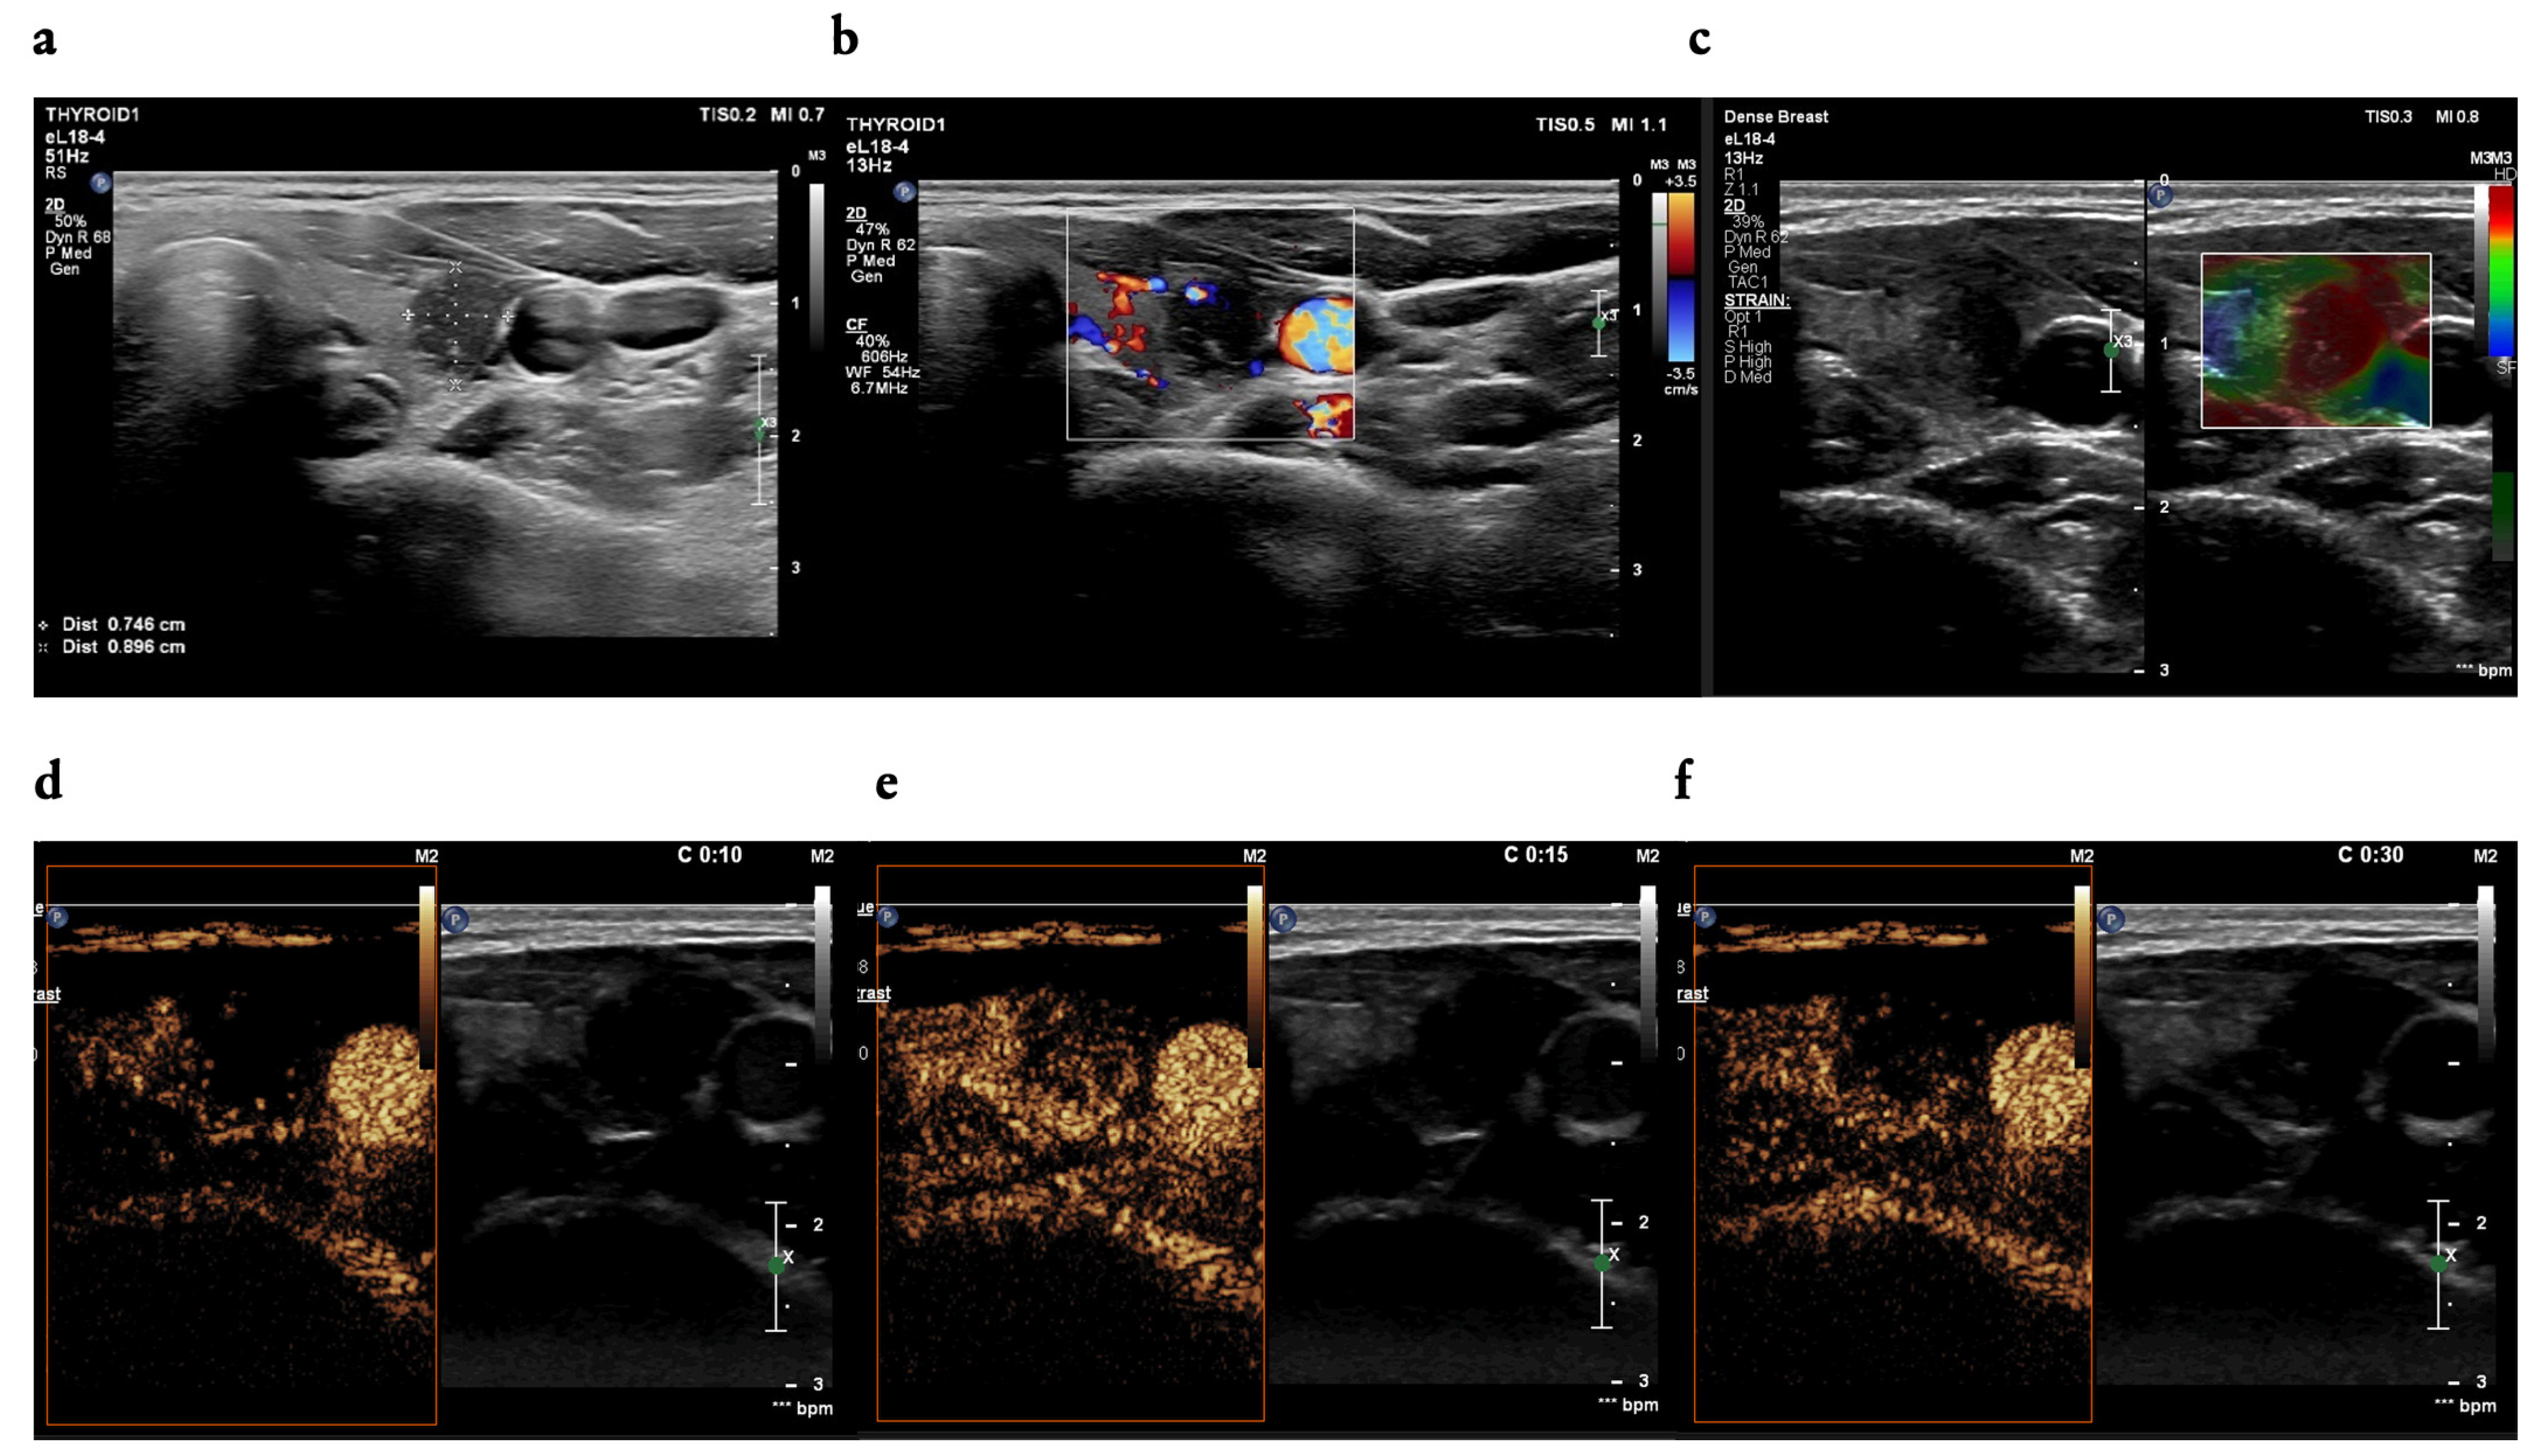

3.2. B-Mode Findings

3.3. CEUS Findings

4.4. The Utility of CEUS Patterns Assessed in the Study in Line with the Literature Review—Malignant Nodules

4.5. The Utility of CEUS Patterns Assessed in the Study in Line with the Literature Review—Benign Nodules